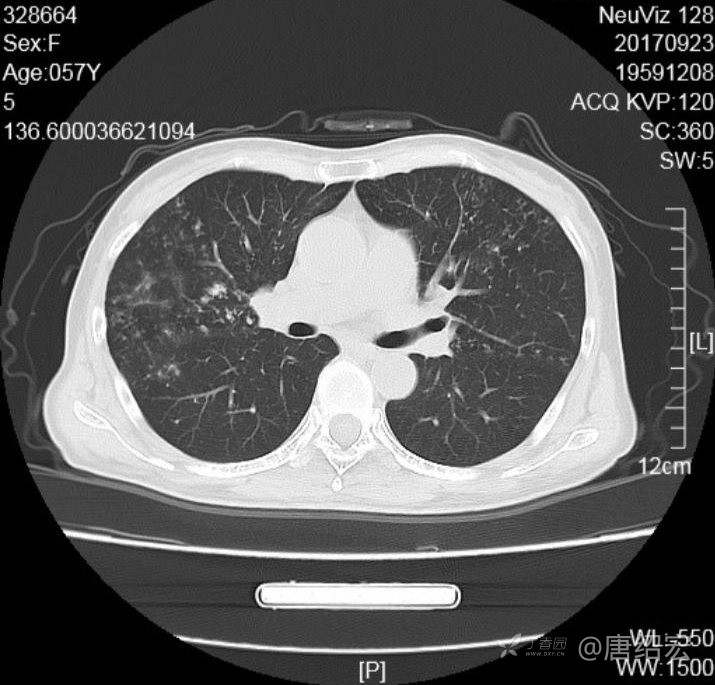

中年女性满肺树芽征还有支气管扩张,考虑什么疾病?

女,57岁,

主诉:发热、咳嗽、咯黄痰,胸闷3天入院。